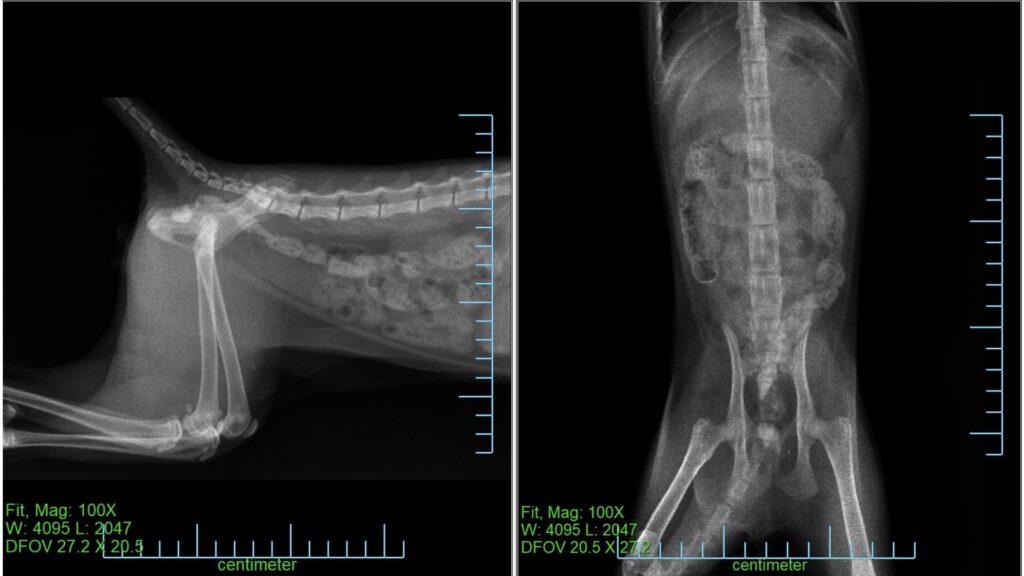

翌々日(3月19日)の経過

翌々日の再診では

• 元気

• 食欲

• 排便

すべて問題ありませんでした。

便の中から長いシリコン製の紐状異物が排出されていることが確認できました。

レントゲン検査でも異常はみられず、この時点で飲み込んだ異物のほとんどが排出されたと判断しました。

経過観察終了となりました。